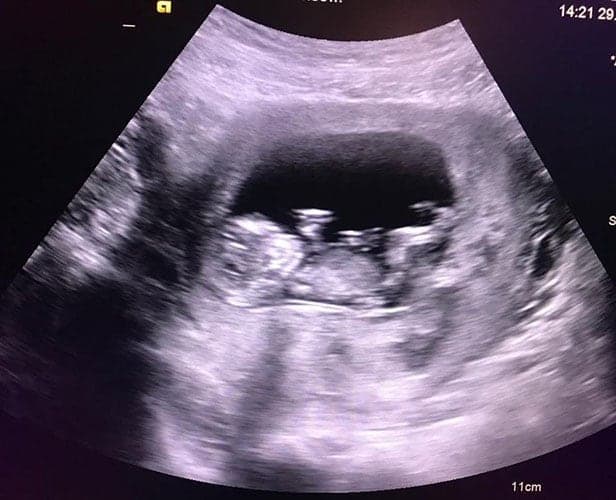

Ultraschallbilder aus dem 1. Trimester (1. SSW bis 12. SSW)

Im ersten Trimester sind die Ultraschallbilder meist noch schwer zu deuten. Oft erkennt man in den letzen Wochen des ersten Trimesters gut den Körper, den Kopf und die Gliedmaße. Das Geschlecht kann man in dieser Zeit meist noch nicht erkennen.